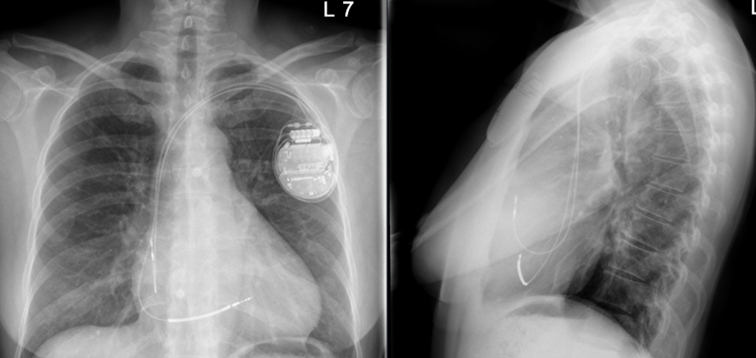

Röntgen-Thorax

Bild 7: Postoperatives Röntgen-Thorax in a.p. und lateral.

In der postoperativen Kontrolle nach 6 Wochen zeigten sich eine regelrechte Systemfunktion und 98 % LBBAP-Stimulationsanteil mit vergleichbarem QRS wie zur Implantation, obwohl über die ICD-Elektroden letztlich nur bipolar stimuliert werden kann.